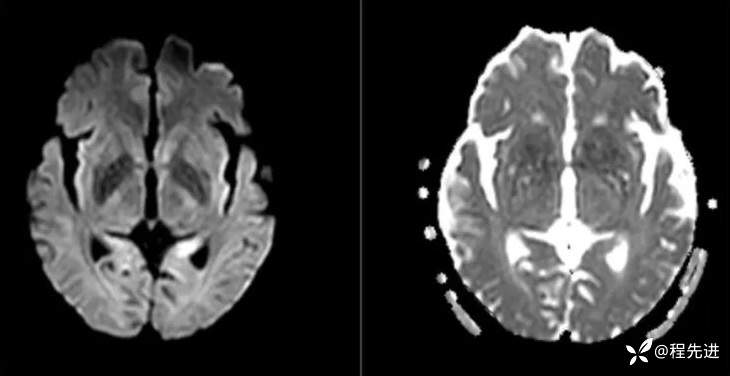

DWI、ADC: